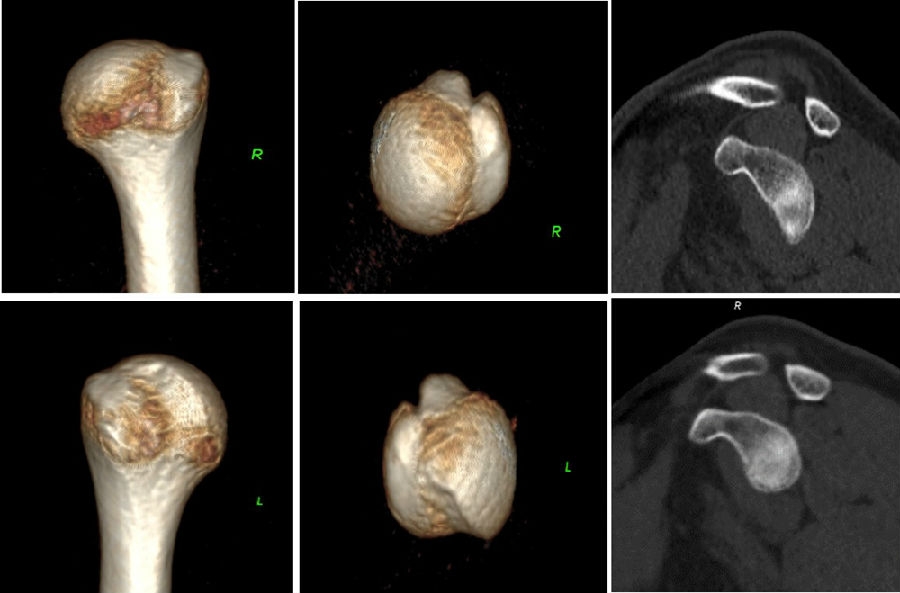

双侧CT三维扫描显示:健侧肩胛盂宽度D=25.9,患侧D=23.9,患侧肩胛盂骨性缺损d=6.2,骨性盂唇缺损面积d/D为23.9%(<25%)。肩胛盂轨迹GT(83%D-d)为15.3mm。

图28双侧CT三维扫描

图29 Hill-Sachs间隙为13.8mm(<15.3mm)

图30 评估结果

评估报告提示:右肩胛骨关节盂前下缘撕脱骨折,符合骨性bankart损伤。右肱骨头后上缘凹陷骨折,符合Hill-Sachs损伤。Hill-Sachs间隙为13.8mm(<15.3mm),为轨迹内肩关节前脱位。